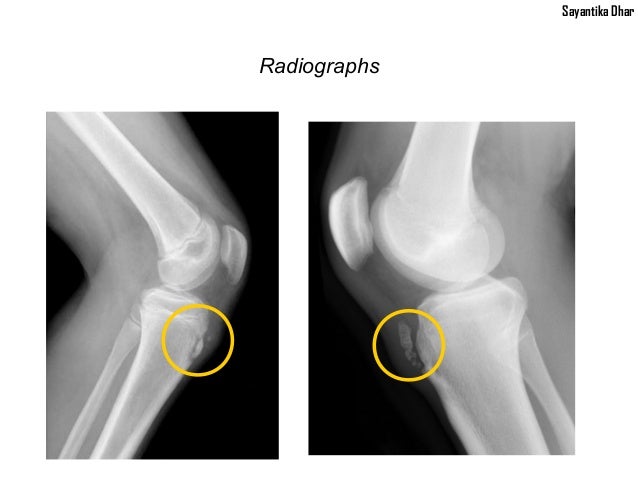

Osgood–Schlatter disease. Osgood–Schlatter disease (OSD) is inflammation of the patellar ligament at the tibial tuberosity (apophysitis). It is characterized by a painful bump just below the knee that is worse with activity and better with rest. Episodes of pain typically last a few weeks to months.

Osgood-Schlatter disease is a condition that causes pain and swelling below the knee joint, where the patellar tendon attaches to the top of the shinbone (tibia), a spot called the tibial tuberosity. There may also be inflammation of the patellar tendon, which stretches over the kneecap.

The findings indicate a strong association between Osgood-Schlatter disease and patella alta. This increase in patellar height would require an increase in the force needed from the quadriceps to achieve full extension. This mechanism could be responsible for the apophyseal lesion.

Why is there a bone sticking out below my knee?

Osgood-Schlatter disease is caused by irritation of the bone growth plate. Bones do not grow in the middle, but at the ends near the joint, in an area called the growth plate. While a child is still growing, these areas of growth are made of cartilage instead of bone. The cartilage is never as strong as the bone, so high levels of stress can cause the growth plate to begin to hurt and swell.